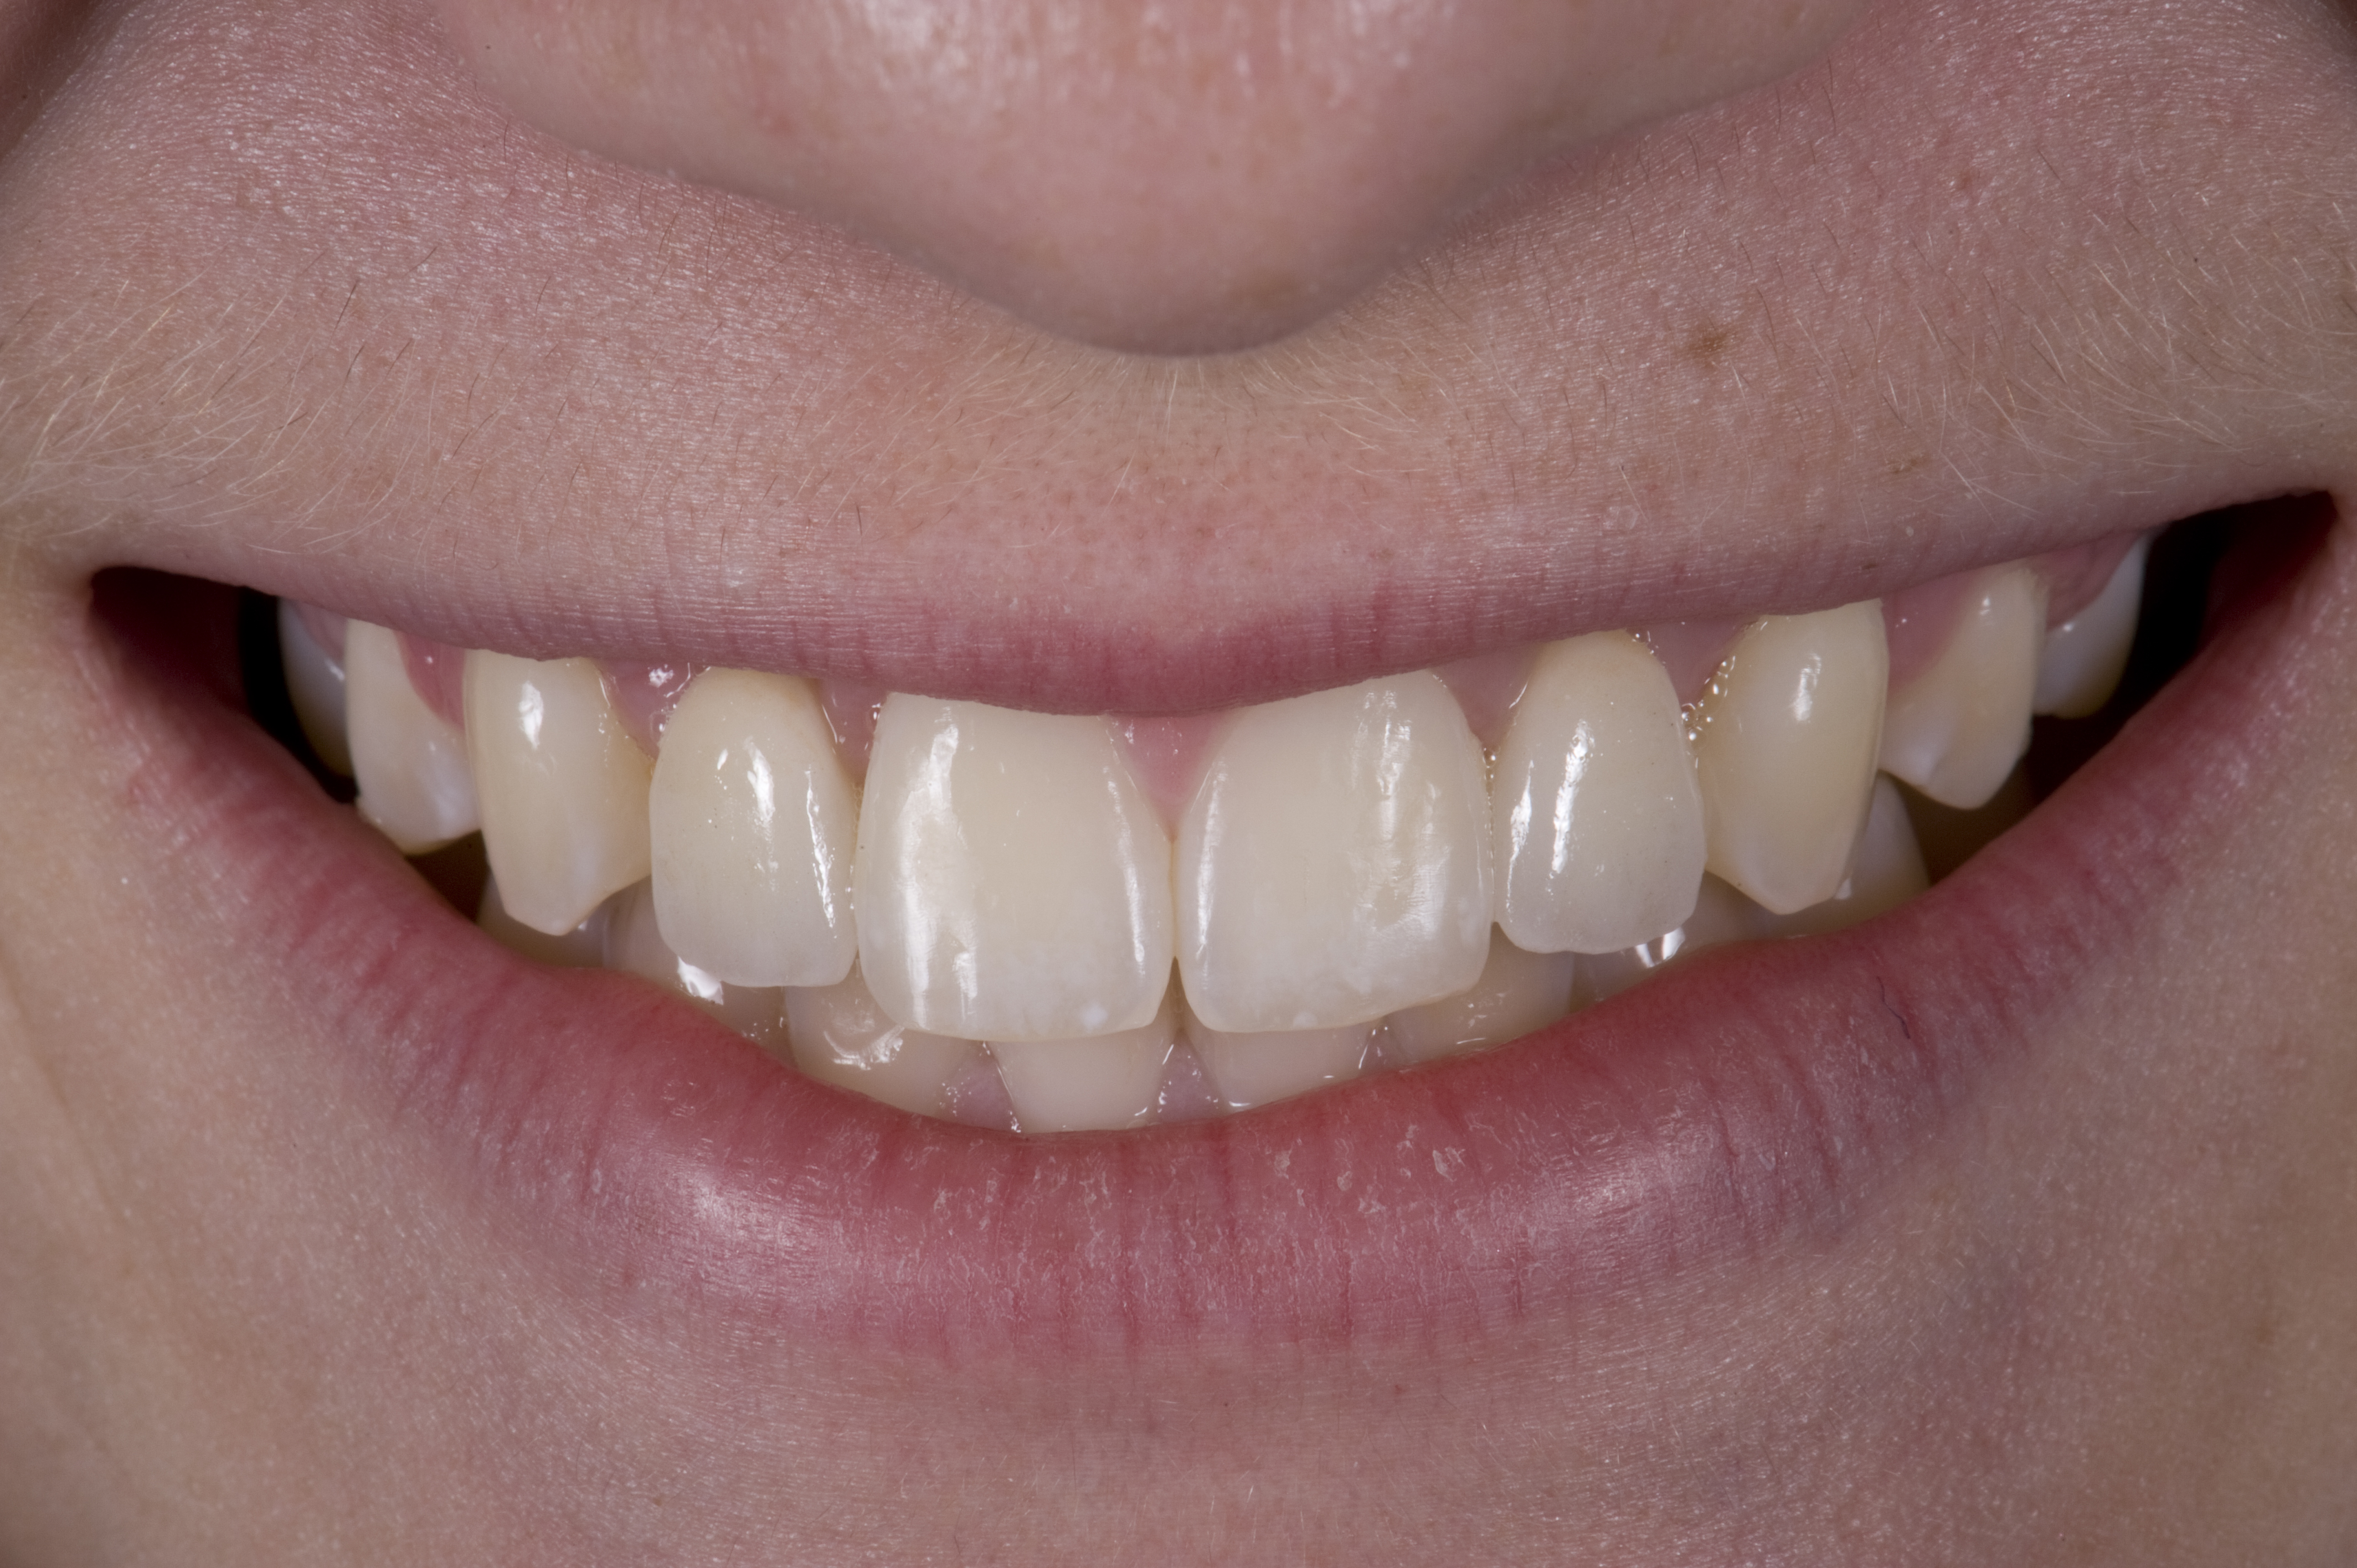

(21.) Smile view.

Figure 21

When the patient returned, the fit was evaluated in the mouth. Once verified, the internal surface of the framework was etched with a 9.5% hydrofluoric acid for 90 seconds and then salinized. After etching the enamel surface with phosphoric acid for 30 seconds and applying the primer (Single Bond Plus, 3M ESPE) to both the internal surface of the framework and the enamel, the zirconia bridge was bonded with a dual-cure resin cement (RelyX™ ARC, 3M ESPE). After the procedure, the patient ended up with a long-term, high-strength esthetic restoration advantaged by the bonding potential of fledspathic ceramic (Figure 20 through Figure 24). Six years after placement, the prosthesis had remained in place with no complications.